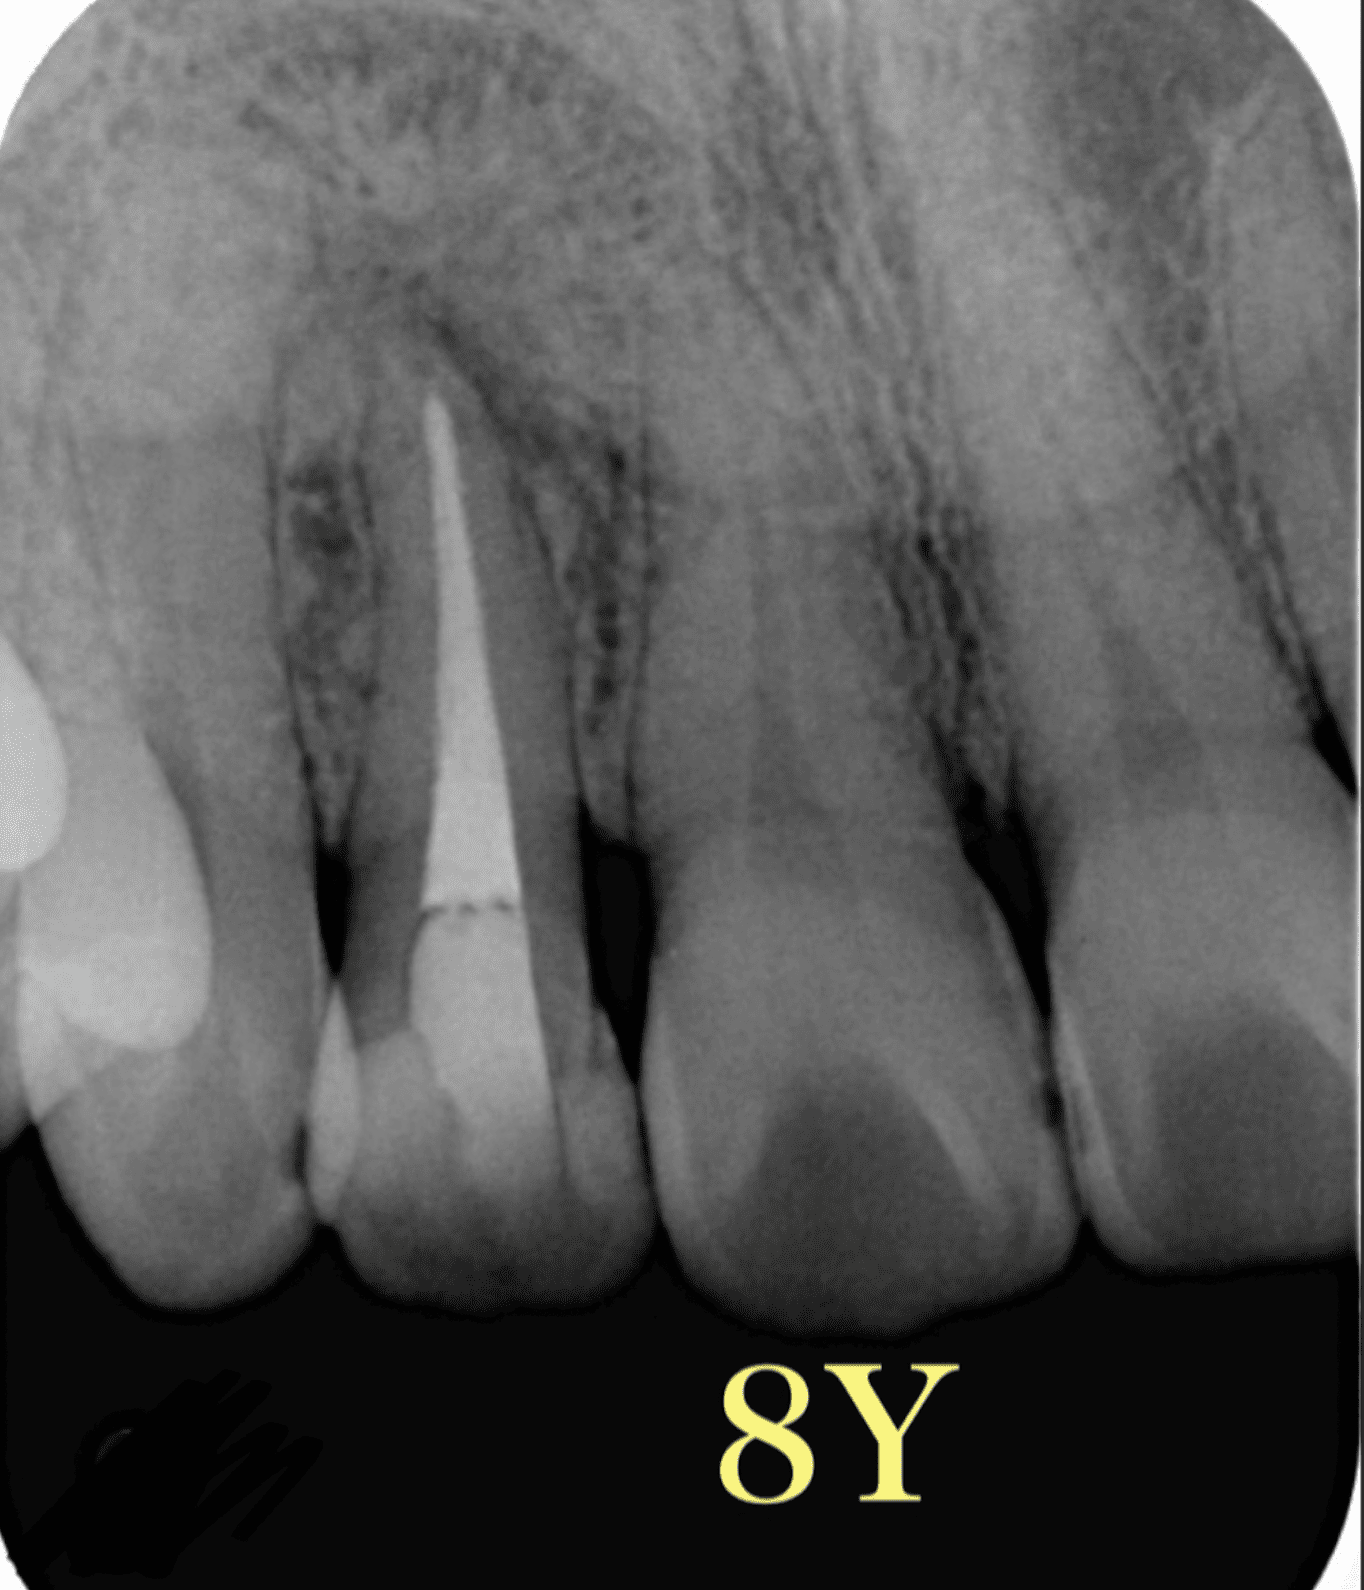

再根管治療後1年で病変の大きさに変化なく、ここで外科治療に踏み切りたくなりますが。。

5年後

だいぶ病変が縮小しました。

根管治療はやはり大事である

ということを示す一例。

そして、症状がないのであれば経過を追う!